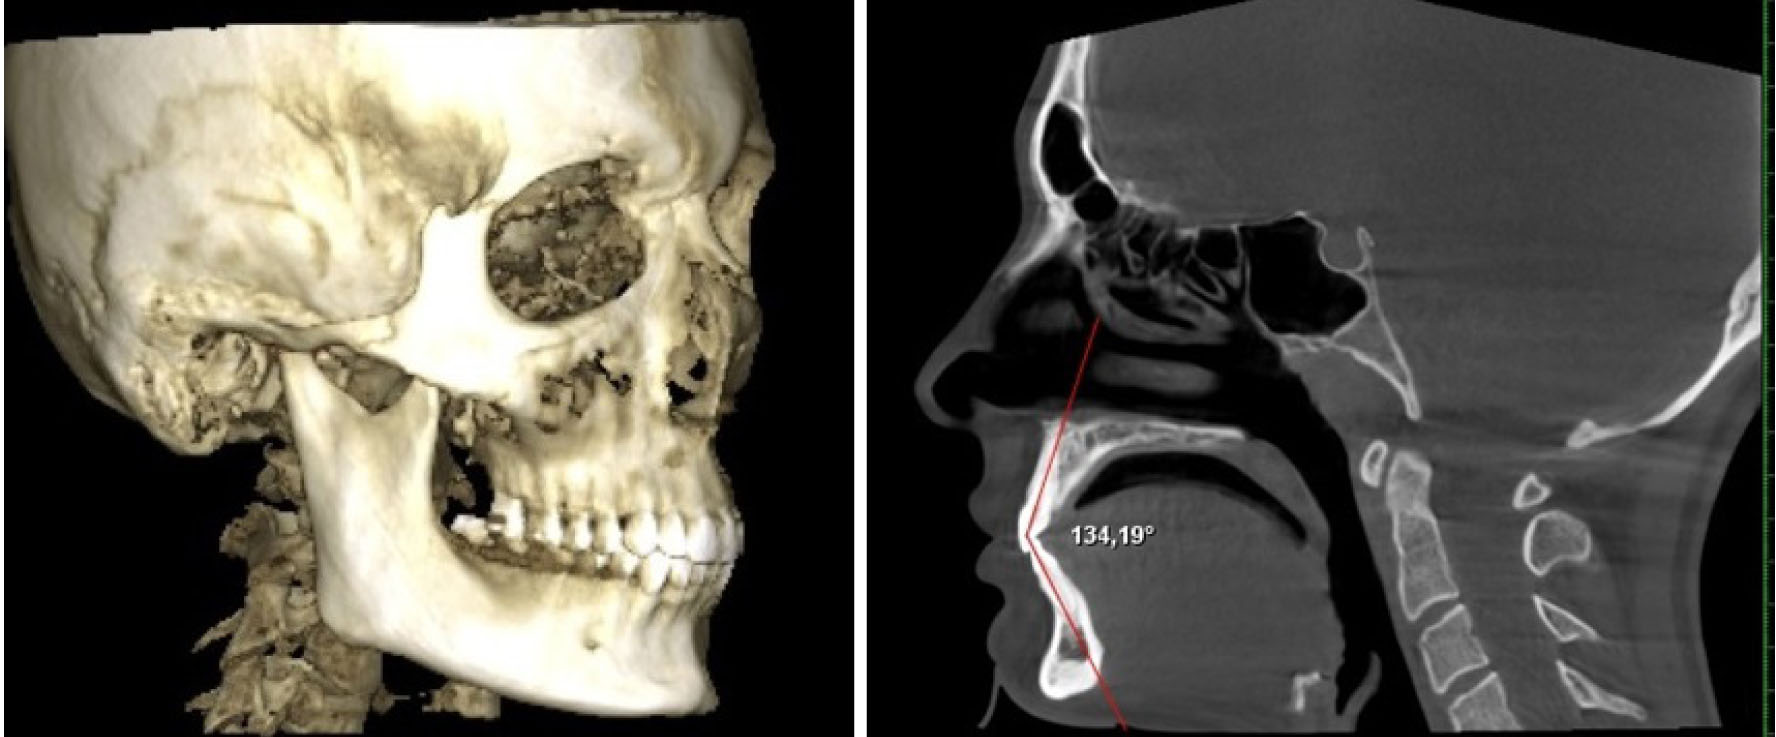

Состояние окклюзии оценивали на объемном снимке черепа, а положение передних зубов – в сагиттальной проекции (рис. 1).

Рис. 1. Объемный снимок головы и определение межрезцового угла в сагиттальной проекции

Межрезцовый угол измеряли между условными срединными вертикалями медиальных резцов, что позволяло определять трузионный тип зубо-челюстных дуг.

Ширину лица измеряли как непосредственно на пациенте между трагиональными точками верхней части козелка, так и на КЛКТ между суставными головками. Измерение ширины лица позволяло определить его соразмерность с шириной альвеолярных дуг обеих челюстей.